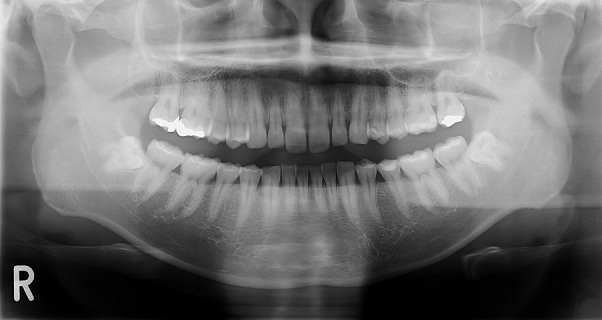

オルソパントモグラフィー(歯科撮影)

オルソパントモグラフィとは、口の中全体を見るためのレントゲン撮影です。

あごの部分をあたかも骨を切り開いたかのように平面に撮影することができます。 これにより歯や歯周、あごの骨の状態をレントゲン写真上で確認することができ ます。レントゲン写真では硬いもの(歯・骨・金属)が白く写り、柔らかいもの (歯茎・神経)は黒く写ります。